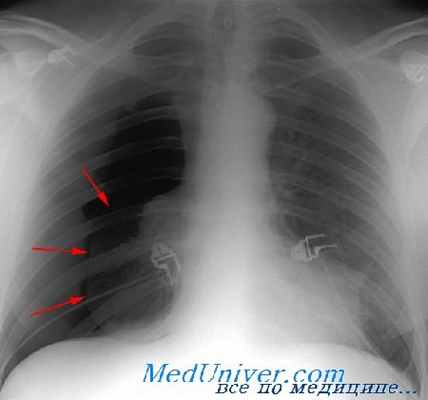

Окончательный диагноз пневмоторакса делается по рентгенограмме, хотя его можно часто заподозрить при физикальном исследовании. Обнаружение подкожной эмфиземы после тупой или проникающей травмы указывает на пневмоторакс. В то время как ослабленные дыхательные звуки — полезная находка, при их наличии, относительно сильный окружающий шум в большинстве травматологических смотровых и факт, что звуки дыхания часто хорошо передаются от другого легкого, лишают этот признак универсальности, а наш опыт показывает, что звуки дыхания могут присутствовать даже при наличии существенного пневмоторакса. Открытая рана на грудной стенке с очевидным выходом воздуха, безусловно, говорит об открытом пневмотораксе.

Как уже сказано, диагноз пневмоторакса обычно ставится по рентгенограмме в переднезадней проекции, выполненной на портативном аппарате. Хотя недавно было показано, что УЗИ имеет значение в диагностике гемопневмоторакса. Это особенно верно при тех передних пневмотораксах, которые плохо видны при рентгенограмме в переднезадней проекции в положении лежа на спине. Предполагалось, что исследование обеих половин грудной клетки должно быть частью прицельной сонографии живота при травме (FAST). Ультразвуковой диагноз пневмоторакса может быть поставлен при визуализации плевры между эхогенными реберными окнами и поиске характерных признаков пневмоторакса.

Часто оценка объема пневмоторакса используется для определения его клинического значения. Это выполняется определением расстояния от поджатого края легкого до грудной стенки в процентном отношении к общему размеру половины грудной клетки. Поскольку КТ живота стало более обычным для оценки пациентов в стабильном состоянии после тупой травмы, выяснилось, что у многих пациентов с тупой травмой есть значительные передние пневмотораксы, которые не видны при обзорной рентгенографии грудной клетки. Частота пропущенных при рентгенограмме в переднезадней проекции в положении лежа на спине пневмотораксов оценивалась в 20-35%.

Размер пневмоторакса, выраженный в процентах от объема гемиторакса, занятого воздухом, может быть оценен на основании результатов рентгенографического исследования Диагностика Пневмоторакс – это скопление воздуха в плевральной полости, что приводит к частичному или полному коллапсу легкого. Пневмоторакс может развиваться спонтанно, в результате травм или медицинских. Прочитайте дополнительные сведенияЛечение травматического пневмоторакса